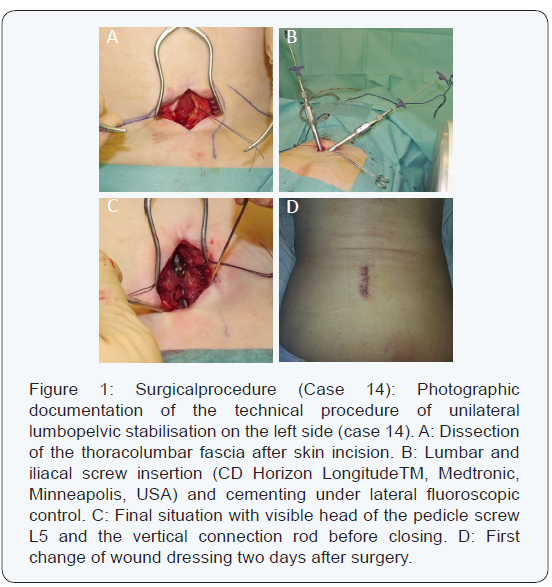

All surgeries were performed by the first, second or last author. Bilateral stabilisations were done by two surgeons. All procedures were performed in a prone position with standardised padding of all contact points, and the same polyaxial multi-level system (CD Horizon LongitudeTM, Medtronic, Minneapolis, USA) was used for dorsal instrumentation. In cases of unilateral mobilisation, the skin incision was done approximately 3cm paramedian to the midline incision, starting from the fourth lumbar vertebral body and continuing parallel to the midline to the posterior iliac spine (Figure 1). Incision length did not exceed 5cm. In cases of bilateral lumbopelvic stabilisation, the skin incision was identical on both sides. The thoracolumbar fascia was exposed and split longitudinally, medial to the sacrospinal muscle. To expose the transverse process, the sacrospinal mass was held laterally by a self-retractor. To insert the distal iliac screw, the sacrospinal muscle was partially blunt dissected to expose the anterior and posterior border of the posterior iliac spine. For bilateral lumbopelvic stabilisation, the approaches were carried out successively and tamponade was used to reduce blood loss while performing the other side.

In cases of degenerative scoliosis, previously consolidated vertebral body fracture of L5 or moderate-to-severe anterolisthesis, it is often more difficult to enter the fifth lumbar pedicel. In such cases, we lengthen the lumbopelvic stabilisation up to the forth vertebral body. Under fluoroscopic guidance, the fourth or fifth lumbar pedicle was identified and then opened with a Jamshidi® needle. The pedicel screw was then inserted through the previously placed guide wire. The entry point for the iliac screw was located posteriorly and medially of the posterior iliac spine. The needle was inserted only a few millimetres into the bone towards the supra acetabular region. The screw guide wire was then carefully inserted under fluoroscopic control to secure the direction and under digital control to prevent cortical perforation. If the entry point and the wire direction are correct, this technique should ensure the strongest screw anchorage according the pylon concept [16]. The iliac screw (7.5x55mm) was then inserted, giving particular attention to the depth. If the screw is not inserted properly or the entry point is placed too anteriorly, the screw head may irritate the thoracolumbar fascia and cause chronic pain. Once the pedicle and iliac screw were correctly placed, the vertical connection rod was inserted medial to the sacrospinal muscle. The fascia was closed with care to avoid irritation by the iliac screw head, the subcutaneous tissue was also adjusted and the skin opening was closed. All patients had immediate full weight bearing mobilisation within the first 24 hours after surgery. First radiographic imaging of the lumbar spine and pelvis were done after weight bearing. For patients with cement augmented screws, an additional thoracic radiograph was done to exclude a cement embolus.